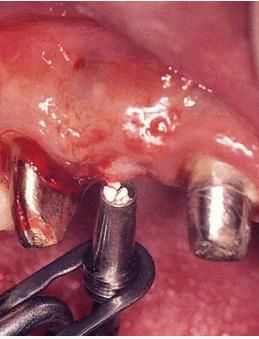

360截圖20170422142001508.jpg

圖16-9    術(shù)后1周。

圖16-10  佩戴最終修復(fù)體時(shí)。